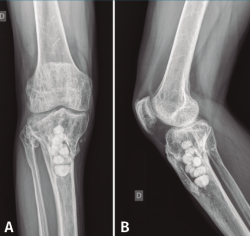

Figura 7. Radiografías de frente y de perfil del extremo proximal de la tibia tras el desbridamiento de la cavidad y el relleno con bolas de cemento con antibiótico.

Con el diagnóstico de osteítis crónica de la tibia se realiza desbridamiento óseo de la cavidad y amplia resección ósea de cortical tibial medial, y relleno de la cavidad con bolas de cemento con antibiótico (Figura 7), con posterior tratamiento antibiótico.

Figura 8. Radiografías del extremo proximal de la tibia donde se objetiva la correcta incorporación del injerto aportado.

Al cabo de 4 meses y tras la resolución del proceso séptico, se procede al relleno de la cavidad con injerto autólogo de cresta iliaca, cuya evolución fue hacia la incorporación de este (Figura 8).